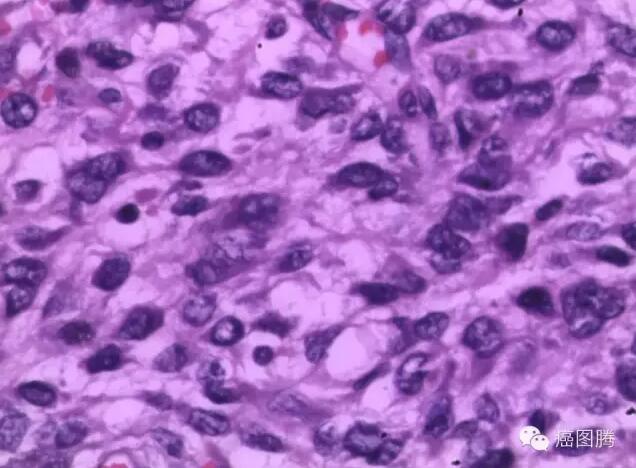

从细胞水平上癌的发生是极偶然的事件,从遗传上癌都是由一个细胞发展而来,由一个失去了增殖控制的细胞发展而来。癌细胞除了生长失控外,还会局部侵入周遭正常组织甚至经由体内循环系统或淋巴系统转移到身体其他部分,不受限制,可以长期增殖下去。癌细胞的基因组、形态结构和细胞表面均发生了变化,细胞膜上的糖蛋白等物质减少,细胞彼此之间的粘着性减小,癌细胞容易在有机体内分散和转移。来源于间叶组织的恶性肿瘤称为“肉瘤”,多发生于皮肤、皮下、骨膜及长骨两端,多见于年轻人。异形细胞占据全层但没有突破基底膜的称为原位癌或上皮内癌,多见于老年人。白血病亦称作血癌,是造血干细胞的恶性增生性病变,其克隆中的白血病细胞失去进一步分化成熟的能力而停滞在细胞发育的不同阶段。

人体组织内侵入了异常细胞或出现了正常情况下不应出现的机体细胞,以及某些病变组织向周围扩展的现象。在细胞内或间质中出现异常的物质或原有的某些物质的堆积过多也称为浸润。浸润也可见于治疗中,除了为了治疗目的使用药物浸润以及炎症灶中各种炎细胞浸润外,其他任何浸润对机体都是有害的,其损害的大小要看浸润的物质的性质、多少以及受累器官功能的影响而定。恶性肿瘤细胞可以浸润周围的正常组织,在质和量方面异常地分布于组织间隙的现象,这称为肿瘤细胞浸润,是肿瘤细胞粘连、酶降解、移动、基质内增殖等一系列过程的表现,往往是恶性肿瘤的特征。